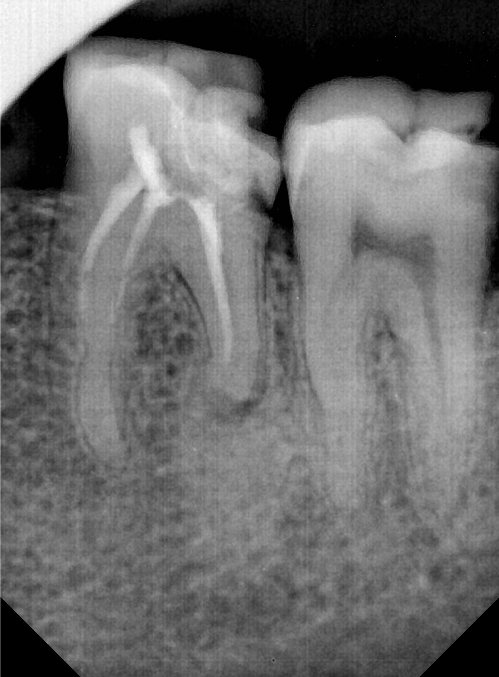

CR/DR 牙齿分割阶段记录

当前进展

- 完成了 CR/DR 牙齿相关分割训练

- 当前结果已经达到阶段预期,但仍有细节问题需要继续处理

相关测试

遇到的问题

- 训练过程中出现过 mask 下移问题

- 部分结果会出现 box 填充异常

- mask 边缘仍然有比较明显的锯齿感

参考

第二版算法问题测试